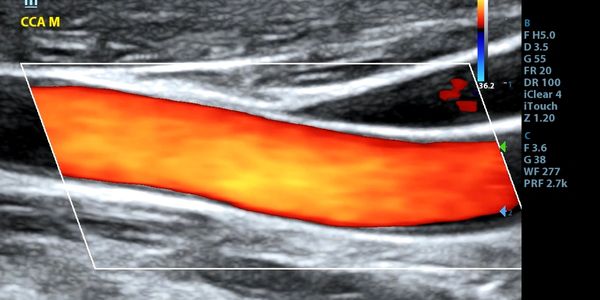

Premier Provider of Mobile Cardiovascular Ultrasound Solutions

ADVANCED SONOGRAPHY LLC.